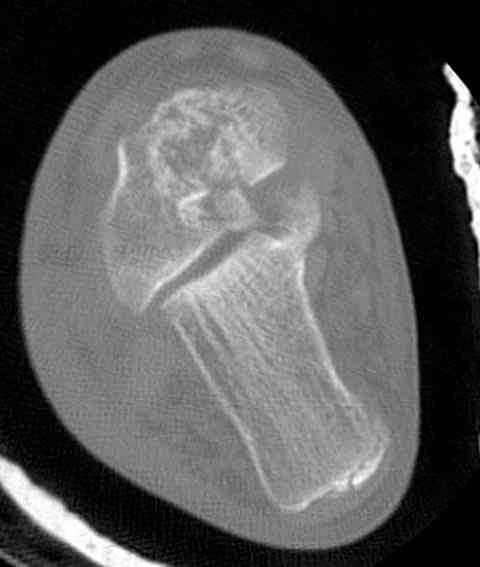

И второй случай из недавней ташкентской практики, (извините за качество ренгенограммы и только в одной проекции) случай падения с высоты (кстати моего друга - известного киноактера) - открытый

смещенный перелом тарана, с переломом переднего края дистального эпиметафиза большеберцовой кости.

При поступлении в приемной сделана первичная обработка с ушиванием открытой латеральной раны и вытяжением за пятку.

Из-за отсутствия времени пришлось оперировать на второе утро, из материала, что имеем на месте, фиксирован двумя шурупами, а третий-это контур сломанного жойстика в 4 мм. На дистальный медиальный конец тибиа antiglide 3.5 мм пластина. Через пару дней выписан и несмотря на предупреждение, самостоятельно начал нагрузку в 4 недели, время не ждет, снимается в боевике в Росийской Федерации.